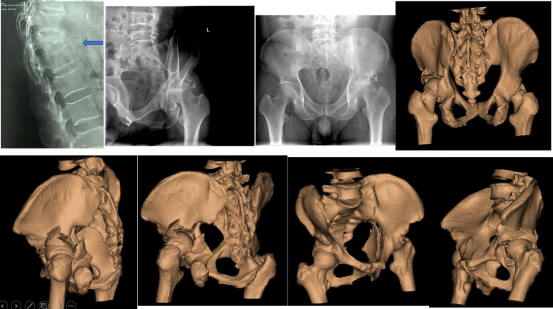

图3 患者李某术前影像资料

9.2日继续完善影像学检查,联系手术室、麻醉科协调手术安排,同时利用数字骨科技术对患者进行术前规划、手术模拟,安排髋臼骨折患者患者髋臼3D打印;

9.3日确定手术方案、手术时间、手术人员等安排;拟9.4给患者周某进行“颈2骨折切开复位椎弓根钉系统内固定术”,拟9.5日给患者李某行“髋臼骨折切开复位内固定、胸12骨折切开复位内固定术”。

9.4日患者周某手术顺利完成;9.5日患者李某手术顺利完成。

9.7日复查术后X片,患者李某可在床上自由翻身,患者周某恢复正常活动。